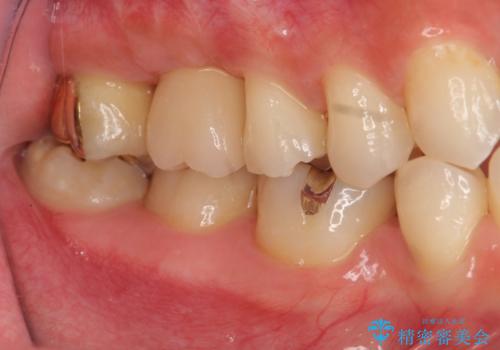

ソケットリフトを伴うインプラント補綴

治療症例の内容

- 右上の歯を喪失し機能回復を希望され来院されました。

骨量が不十分であった為、ソケットリフトを併用しインプラントによる補綴計画を立てます。

- 50万円(ストローマンインプラント・ソケットリフト・ジルコニアカスタムアバットメント・ジルコニアクラウン)費用は治療当時の料金となります

上顎のインプラントは、上顎洞底までの距離が短い場合ソケットリフト法を行い骨量を増やしたのちにインプラント埋入を行うことでより長期的な予後を見込むことができます。